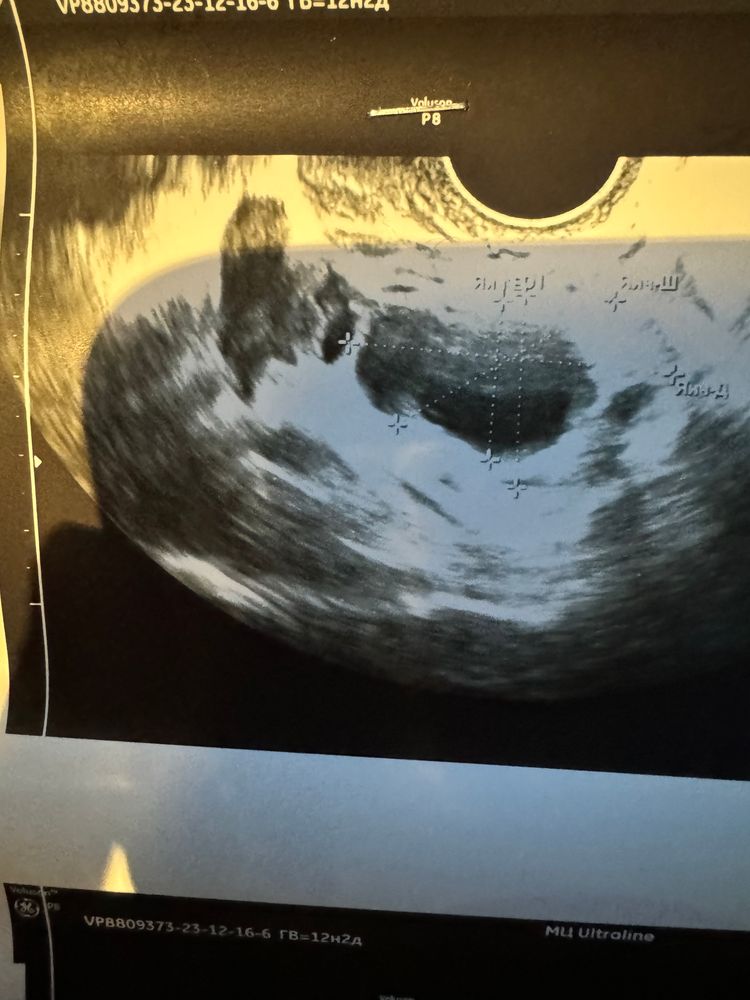

Вчера по ощущениям была овуляция, плюс микроскоп показал овуляцию, сегодня на узистка сказала это доминантны фолликул 19мм, не желтое тело. Кто понимает?